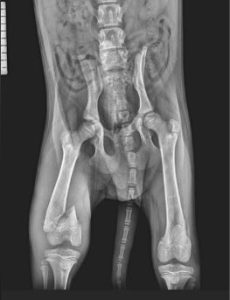

Jamie and his two siblings were found abandoned in a derelict school house. Desperation was etched on their sweet faces and their bodies were full of fleas and their skin covered in demodex. Jamie was found to be less active than his siblings and after x-rays was found to have a fractured femur. He has now had an operation and is recovering from his ordeal alongside his brothers